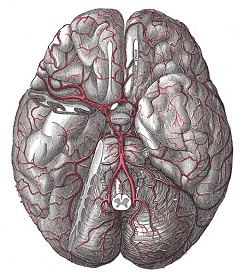

Виллизиев круг (circulus arteriosus cerebri Willisii) - это анастомоз между вертебрально-базилярной и каротидной системой кровоснабжения головного мозга. Он находится в основании головного мозга и представляет собой сеть артерий, имеющую форму овала с наименьшим поперечным диаметром. Свое название это анатомическое образование получило по фамилии английского врача, впервые описавшего его.

- Начальная часть задней мозговой артерии;

- Соединительная задняя артерия;

- Супраклиноидная часть внутренних сонных артерий;

- Передняя соединительная артерия;

- Начальная часть передней мозговой артерии.

Виллизиев круг соединяет каждую из сонных артерий не только между собой, но и с системой позвоночных артерий. При нормальном развитии Виллизиева круга его правая и левая половины имеют симметричное строение.